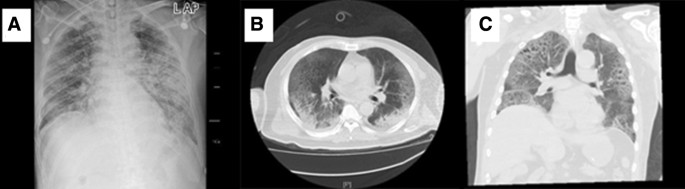

Fig. 1

figure 1

The chest imaging of patient 2. a Bedside chest radiograph on the first day of admission. b, c Computerized tomography on the 9th day showed ground-glass changes typical of viral pneumonia

Numerous differences in laboratory findings were identified between the patients admitted to the ICU and those not admitted to the ICU (Table 2), including lower red blood cell and lymphocyte counts, higher white blood cell counts and fibrinogen, D-dimer, brain natriuretic peptide (BNP) and blood urea nitrogen levels, and longer prothrombin times in the ICU patients. Meanwhile, C-reactive protein, procalcitonin, and interleukin 6 (IL-6) levels were also higher in the ICU patients than in the non-ICU patients. Regarding myocardial injury markers, TnI and myoglobin (MYO) levels were significantly higher in the ICU patients, and the measurements for ICU vs non-ICU patients were as follows: TnI (0.029 ng/mL [0.007–0.063] vs 0.006 ng/mL [0.006–0.006]) and MYO (65.45 μg/L [39.77–130.57] vs 37.00 μg/L [26.40–53.54]). More patients presented with elevated TnI and MYO levels in the ICU group than in the non-ICU (18/35 [51%] vs 11/310 [4%], 8/26 [31%] vs 22/148 [15%], respectively). In the ICU patients, the median partial pressure of oxygen (PaO2) was 76.65 mmHg (IQR, 59.10–96.60), and the median partial pressure of oxygen to the fraction of inspired oxygen ratio (PaO2/FiO2) was 267.38 (IQR, 145.50–355.17), which were significantly lower than the values for the non-ICU patients. All patients’ chest X-rays and/or chest CT scans showed distributed patchy shadows or ground-glass opacities (Fig. 1).